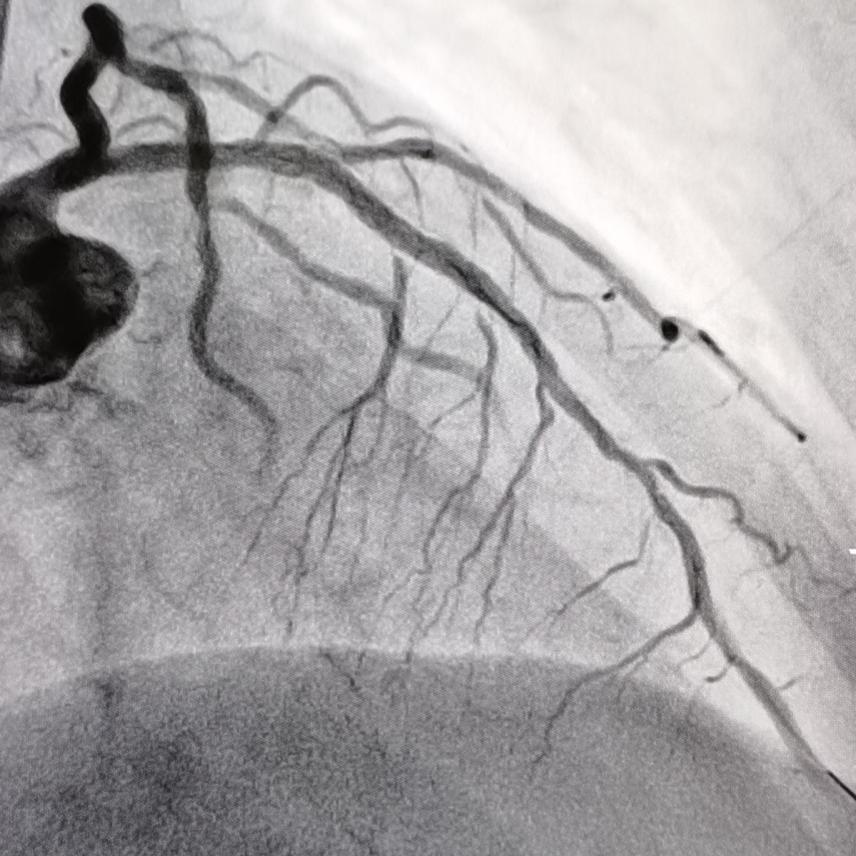

冠状动脉 旋磨

老人冠状动脉钙化硬如"磐石" 医生用金刚钻来旋磨打通血管!

冠状动脉旋磨术是采用呈橄榄型的带有钻石颗粒旋磨头,根据差异切割及

冠脉旋磨术用物理的方法将动脉硬化斑块祛除,虽然技术难度高,但对于

旋磨术主要适用于解剖学上高危的病变,如钙化的病灶,开口处病灶,球囊